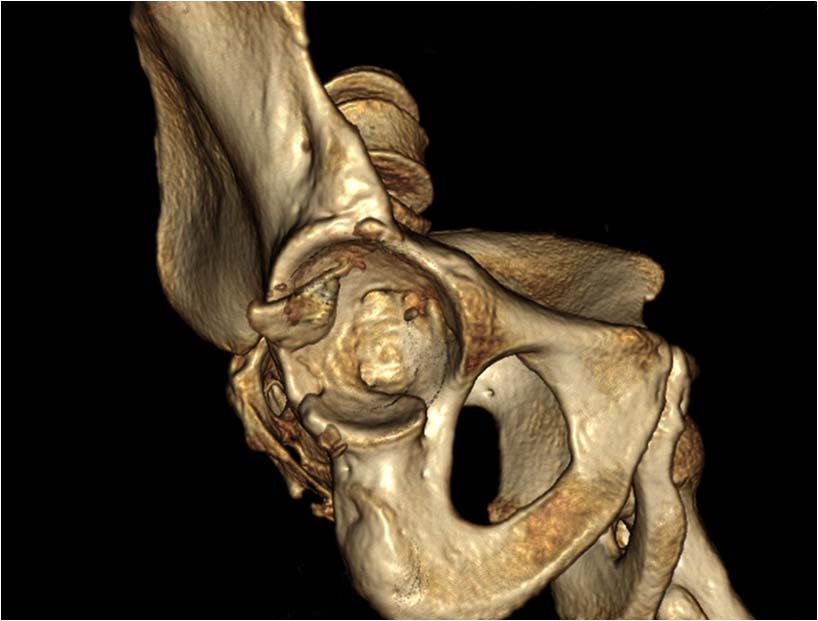

Мужчина, 46 лет, пострадал в результате ДТП (водитель). Удар пришелся

через согнутое правое колено об приборную панель, что привело к заднему

вывиху головки бедра. При госпитализации кроме вывиха бедра

диагностирован перелом нижнего сегмента головки бедра и закрытый перелом

с/3 правого плеча (АО 12-В2).

При поступлении выполнено закрытое вправление головки бедра, налажено

скелетное вытяжение. Контрольный рентген показал разницу в ширине

суставных щелей в сравнении с неповрежденной стороной. Сделали КТ,

которое подтвердило наличие внутрисуставного фрагмента задней стенки

вертлужной впадины и перелом нижне-медиального сегмента головки со

смещением (Pipkin IV).